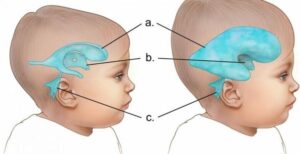

ولفت الى أن الاستسقاء الدماغي هو تراكم السائل الدماغي الشوكي في التجاويف (البطينات) الموجودة في عمق الدماغ مما يؤدي إلى زيادة في حجم هذه البطينات،وبالتالي تحدث ضغطاً على أنسجة الدماغ.

وقال: يتم انتاج السائل الدماغي الشوكي بواسطة خلايا متخصصة موجودة داخل البطينات الدماغية ويتم افرازه إلى تجاويف هذه البطينات،وفي الوضع الطبيعي يتدفق هذا السائل من خلال البطينات ويدور حول الدماغ والحبل الشوكي،ولكن الضغط الذي يحدثه فرط السائل الدماغي الشوكي يمكنه أن يلحق ضرراً بأنسجة الدماغ مسبباً مجموعة من الأعراض مرتبطة بوظائف الدماغ.

وقال: تختلف الأعراض أيضاً حسب العمر وأكثر الأعراض شيوعاً هي الشعور بالغثيان والقيئ، الصداع الشديد،الشعور بالنعاس والخمول،نوبات الصرع،تحديق العينين للأسفل، ضبابية الرؤية، حركات العينين غير الطبيعية، صعوبة في الحركة والتوازن، فقدان التحكم في البول وفقدان الذاكرة وخاصة عند كبار السن،وكذلك زيادة في حجم الرأس وخاصة عند الأطفال الرضع والخدج.